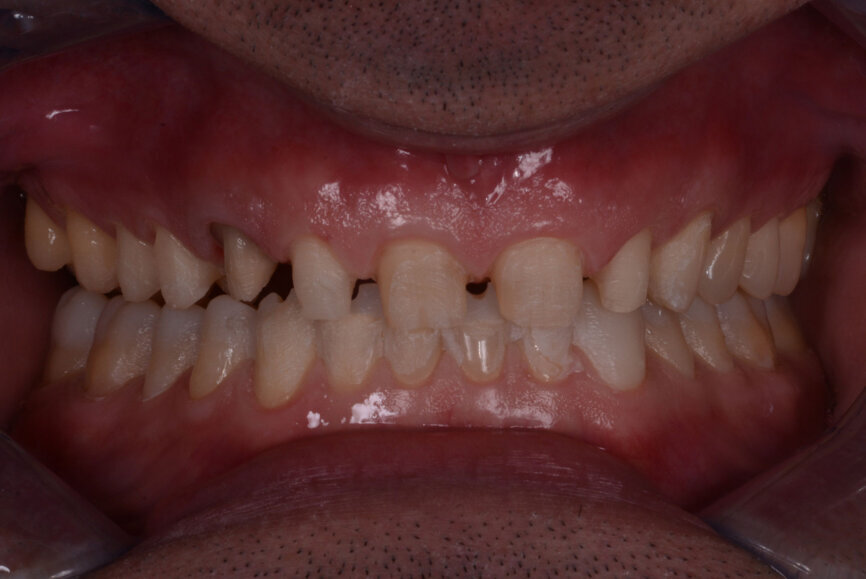

In 2015, a 47-year-old male patient presented complaining of pain in the TMJ. He also had an aesthetic request, since part of the veneer on one of the maxillary central incisors had broken off (Figs. 1–3). The clinical and radiographic analysis (Fig. 4) indicated a loss of bite height and tooth substance due to bruxism.

Fig. 7: Two years later, prior to treatment (2017).